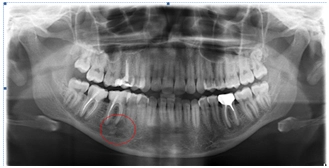

На диагностическом снимке – ортопантомограмме.

В двух жевательных зубах нижней челюсти справа и одном жевательном зубе нижней челюсти слева обнаружены околокорневые кисты. Зубы ранее депульпированы, каналы были пломбированы.

эндодонтия